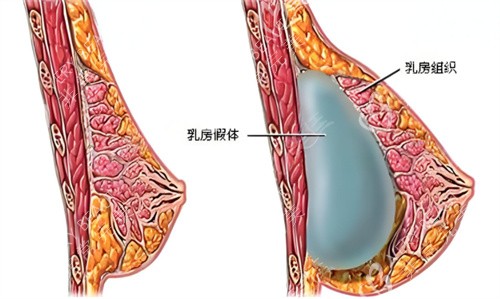

清潭 ok 医院主打 “假体丰胸精细化操作”,医生对假体放置位置的把控特别更准一些。比如做内窥镜假体丰胸时,会通过高清内窥镜避开血管和神经,减少术中出血,术后肿胀轻,修养期比传统手术短 3 - 5 天。医院还和多个出名假体品牌合作,像曼托、傲诺拉等,假体质量有确保。

UcanB 医院在韩国做胸界以 “技术创新” 为亮点,比如推出的 “双平面假体丰胸技术”,能让假体一半在胸大肌下,一半在乳腺下,兼顾了假体的稳定性和胸部的柔软度。术后不管是平躺还是站立,胸型都能保持自然弧度,不会出现假体移位或下垂的情况。

必当归医院是韩国老牌整形医院,做胸的经验特别丰富,尤其擅长 “修复型丰胸”。比如之前做过丰胸手术,出现假体移位、包膜挛缩的顾客,来这里修复的结果比较好。医生会先详细检查胸部情况,制定针对性修复方案,比如取出旧假体后,会对胸部组织进行修复和调整,再植入新假体,术后胸型不仅修养自然,还能解决之前的问题,口碑在修复人群中特别好。